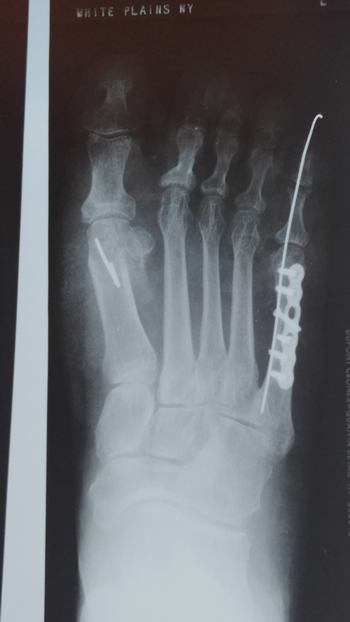

5th digital surgery

Pre & Post-op. Bunion and 5th Digital Surgery

Pre-op